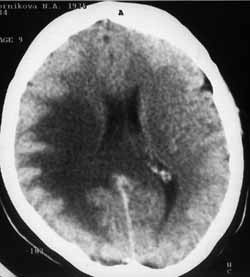

Рис. 3 и 4. (Слева) В правой височно-теменной области отмечается амебовидное снижение плотности белого вещества. После внутривенного усиления накопления контрастного вещества не выявлено. (Справа) Тот же больной. Через 1 месяц четко визуализируется метастаз.